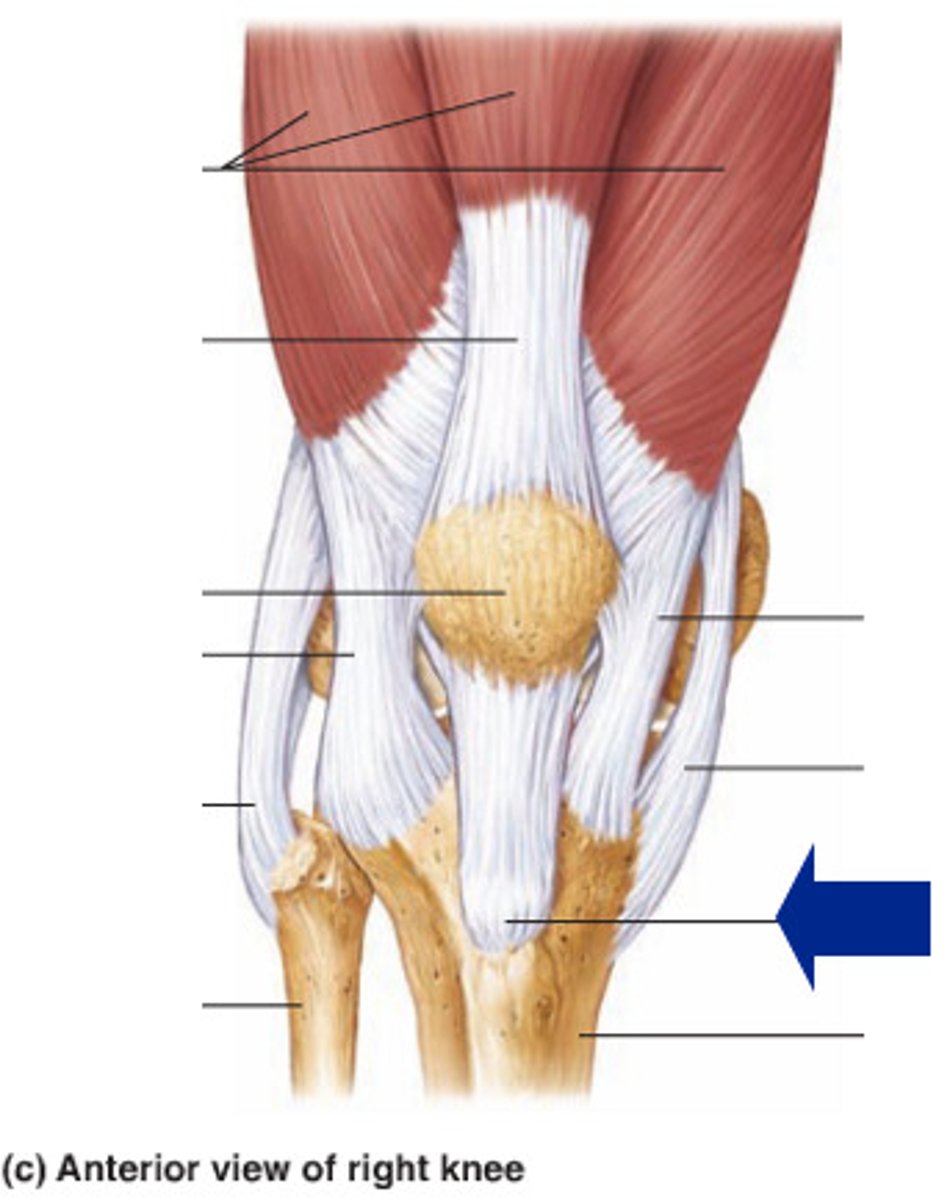

Quadriceps tendon

Patellar ligament

Medial meniscus

Lateral meniscus

Anterior cruciate ligament

Posterior cruciate ligament

Medial (tibial) collateral ligament

Lateral (fibular) collateral ligament